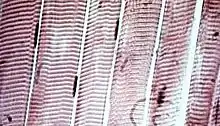

![]() The body contains three types of muscle tissue: (a) skeletal muscle, (b) smooth muscle, and (c) cardiac muscle. (Same magnification) | |

Muscle tissues vary with function and location in the body. In mammals the three types are: skeletal or striated muscle; smooth or non-striated muscle; and cardiac muscle, which is sometimes known as semi-striated. Smooth and cardiac muscle contracts involuntarily, without conscious intervention. These muscle types may be activated both through the interaction of the central nervous system as well as by receiving innervation from peripheral plexus or endocrine (hormonal) activation. Striated or skeletal muscle only contracts voluntarily, upon the influence of the central nervous system. Reflexes are a form of non conscious activation of skeletal muscles, but nonetheless arise through activation of the central nervous system, albeit not engaging cortical structures until after the contraction has occurred.[1]

Muscle tissue is an elongated tissue ranging from several millimeters to about 10 centimeters in length and from 10 to 100 micrometers in width.[2] These cells are joined together in tissues that may be either striated or smooth, depending on the presence or absence, respectively, of organized, regularly repeated arrangements of myofibrillar contractile proteins called myofilaments. Striated muscle is further classified as either skeletal or cardiac muscle.[3] Striated muscle is typically subject to conscious control, while smooth muscle is not. Thus, muscle tissue can be described as being one of three different types:

Cardiac and skeletal muscles are "striated" in that they contain sarcomeres and are packed into highly regular arrangements of bundles; smooth muscle has neither. While skeletal muscles are arranged in regular, parallel bundles, cardiac muscle connects at branching, irregular angles (called intercalated discs). Striated muscle contracts and relaxes in short, intense bursts, whereas smooth muscle sustains longer or even near-permanent contractions.